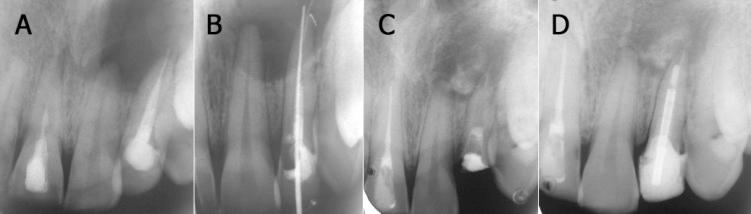

Persistent microorganisms in the root canal are known to cause endodontic treatments failure. Overextended gutta-percha can also act as a periradicular tissue irritant, leading to large periapical lesions. Retrieval of overextended gutta-percha with a nonsurgical approach can prove to be a challenge. This case describes the nonsurgical management of a large periapical lesion associated with overextended gutta-percha. Retrieval of gutta-percha was attempted but the overextended portion could not be removed. Aspiration of the purulent exudate was done through the root canal followed by use of a triple antibiotic paste. After 2 weeks the antibiotic paste was replaced with calcium hydroxide, to enhance the osseous regeneration. The periapical lesion showed a considerable amount of periapical healing after 15 months. The results of this case demonstrate that aspiration in conjunction with the triple antibiotic paste and calcium hydroxide may possibly be used in managing large periapical lesions associated with overextend gutta-percha.

根管内持续存在的微生物会导致牙髓治疗失败。超充的牙胶尖也可作为根尖周组织刺激物,导致较大的根尖周病变。采用非手术方法取出超充的牙胶尖可能具有挑战性。本病例描述了与超充牙胶尖相关的较大根尖周病变的非手术治疗。尝试取出牙胶尖,但超充部分无法去除。通过根管抽吸脓性渗出物,随后使用三联抗生素糊剂。2周后,将抗生素糊剂替换为氢氧化钙,以促进骨再生。15个月后,根尖周病变显示出大量根尖周愈合。本病例结果表明,抽吸联合三联抗生素糊剂和氢氧化钙可能可用于治疗与超充牙胶尖相关的较大根尖周病变。